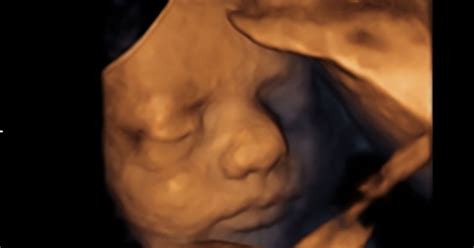

V 27. tednu nosečnosti je otrok že precej razvit. Njegova dolžina dosega približno 34 do 36 centimetrov, teža pa se giblje okoli 1 kilograma. Otrok je zdaj velikosti manjše glave solate ali pomaranče, kar omogoča, da ga lahko z lahkoto primerjamo z velikostjo, ki se prilega na podlaket med roko in komolcem.

- Vid in okus: Otrok lahko zdaj razlikuje med svetlobo in temo ter odpira in zapira oči s pomočjo vek. Na jeziku se razvijajo prve okušalne brbončice, kar pomeni, da lahko otrok okuša različne okuse v plodovnici, ki jo pogoltne. Ta razvoj vida in okusa je tesno povezan z razvojem možganov.

- Možgani: Površina možganov, ki je bila prej gladka, se zdaj prične nagubati, kar omogoča večjo površino za živčne celice. Možganska aktivnost je opazna.

- Telesne proporcije: Proporci otrokovega telesa postajajo vse bolj podobni proporciom ob rojstvu. Glava raste počasneje, da jo lahko preostanek telesa "dohiti". Zaradi pomanjkanja podkožne maščobe je koža še vedno nagubana, vendar se bo to spremenilo z razvojem maščobnih celic.